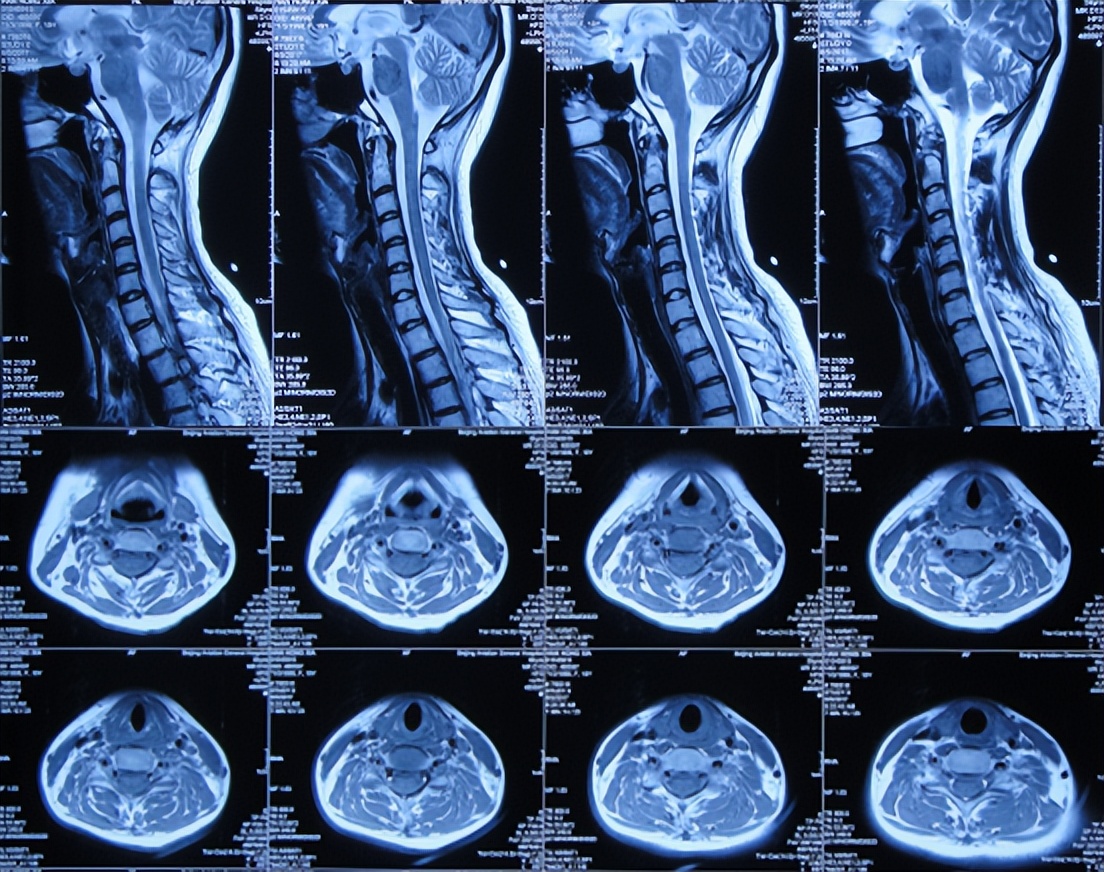

但发病后5天即2017年3月25日,从学校宿舍的上铺下来时因发热虚弱摔下,右眼眶外伤,就诊于第1家的陕西省西安某三甲医院,查脑CT( 图-1 )后认为右额颞部硬膜下有血肿,胸部X线检查未见异常(片子丢失)。

图-1: 2017年3月25日脑CT

2017年4月2日(发病后13天),就诊于第2家的陕西省神木县某医院急诊外科,检查期间突发四肢软瘫、意识丧失、大小便*禁失**,查脑CT( 图-2 )后紧急收入ICU。

图-2: 2017年4月2日脑CT